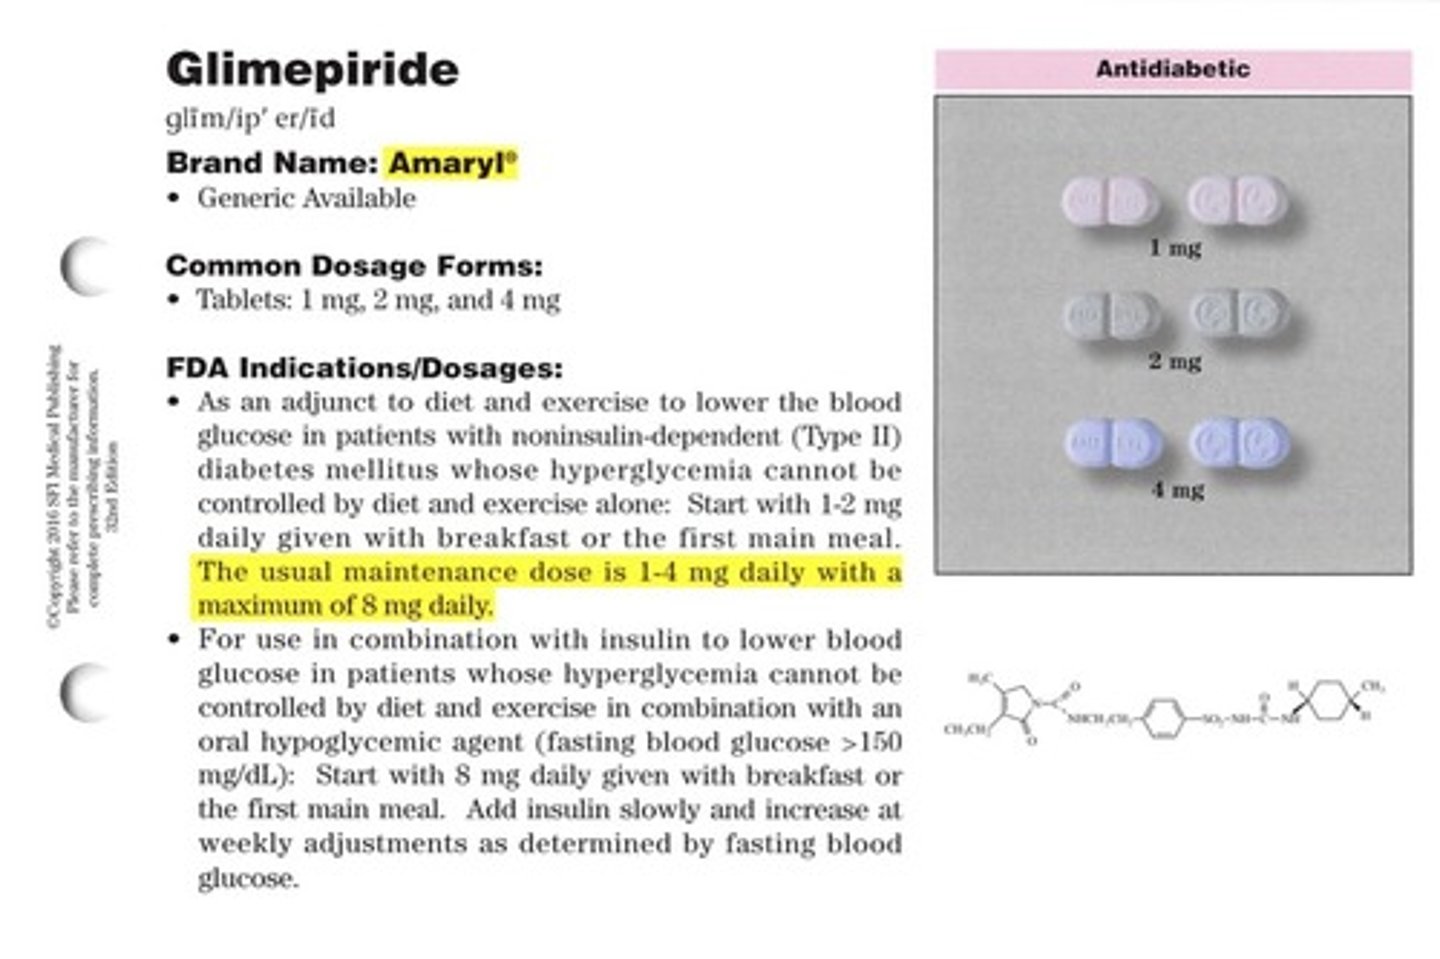

Glimepiride

Brand: Amaryl

Class: Sulfonylurea

Indication: Diabetes Agent

Schedule: NCLM